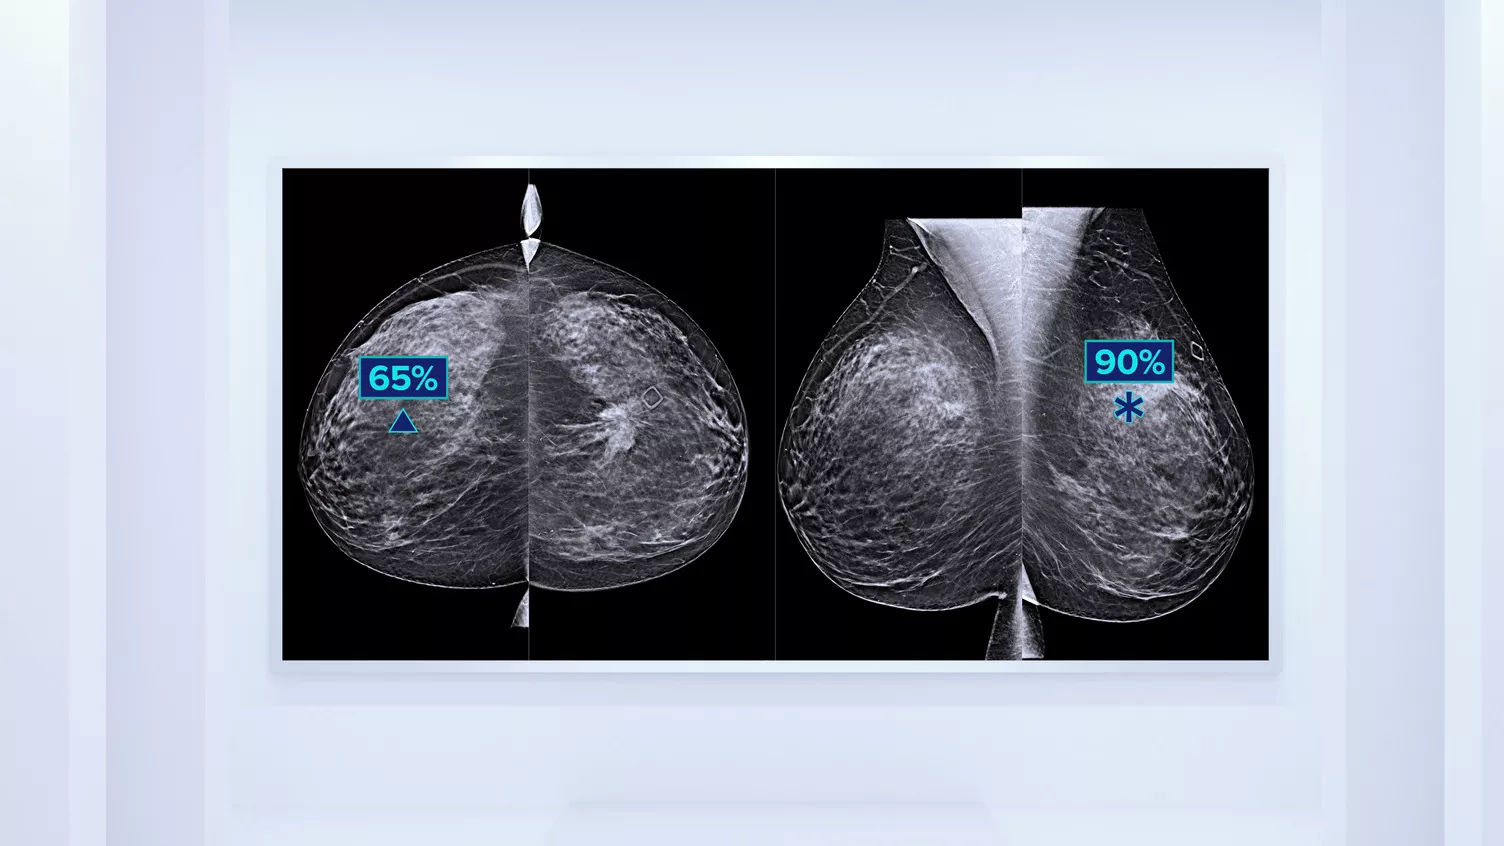

Technologie de détection Genius AI™

Un algorithme d’apprentissage profond conçu pour aider les radiologues à effectuer des diagnostics et à détecter un cancer du sein4,9,10 à partir d’images de tomosynthèse obtenues à l’aide des systèmes de mammographie Dimensions d’Hologic. Il localise les lésions en étudiant chaque coupe de l’ensemble d’images. Les zones suspectes sont mises en évidence pour une lecture simultanée.

On sait qu’une densité mammaire plus élevée augmente le risque de cancer du sein chez la femme.11,12 Une analyse précise et objective s’avère donc primordiale. Grâce à l’apprentissage automatique, le logiciel Quantra analyse la texture et le modèle du tissu mammaire dans les images 2D et de tomosynthèse, et classe les seins dans quatre catégories de risque de composition.13